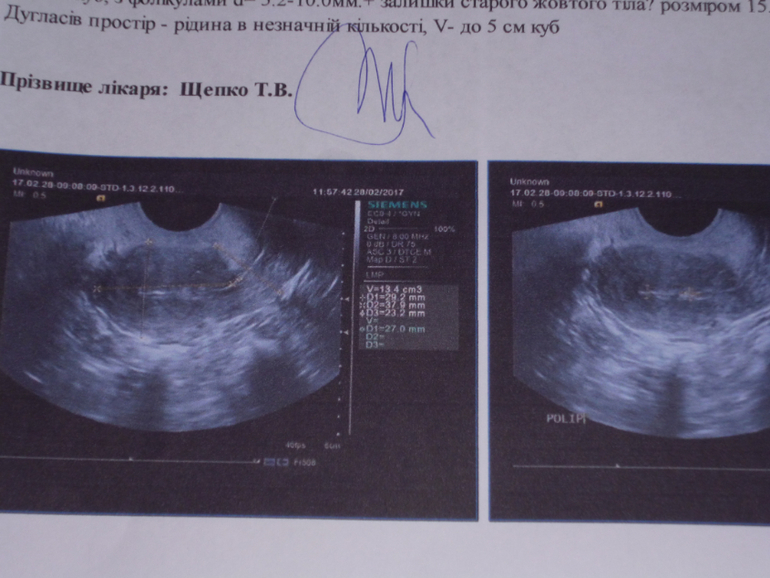

Ура! Мой график беременный!УЗДпосле лапароскопии ,говорят надо гистероскопию!!!!!!!!! ето 2 года обследований,2 операции,2раза прверка труб,гормони,стимуляции,мокрии подушки и отчяянье и еще гистеру надо,ето что порча!!!???кто может что-то сказать поУЗД?а где ДФ??? МОЖЕТ ПОЛИП САМ ИСЧЕЗНУТЬ??

Что за старое желтое тело?? У вас на какой день цикла было УЗИ? Жидкость - один из признаков О по УЗИ.

Да.. на 8 д.ц. появление желтого тела рано... А месячные были месячными? Или незначительные кровяные выделения во время овуляции? Вы отслеживаете базальную температуру? Так же кровяные выделения могут быть не только при овуляции и месячных, но и при имплонтации или маточном кровотечении, вызванного зпп или сбоем гормонов. Просто если есть желтое тело, то должен быть прогестерон, а значит какие месячные? Вообще не слышала понятие про СТАРОЕ желтое тело.... Звучит как бредятина..

Лена

Чтоб судить о наличии Овуляции по графику БТ, нужно знать и температуру 1 фазы. Ибо в среднем во вторую фазу БТ выше 37, а у вас она ниже, это значить может много: либо во время замеров была 1 фаза, а не вторая; либо есть прогестероновая недостаточность; либо в вашем случае такая температура является нормой, если средняя темература первой фазы меньше средней температуры второй фазы на 0,3 и более делений. НО толщина эндометрия у вас по УЗИ соответствует первой фазе. После вывода о старом желтом теле с размерами 15 на 15 узист ставит знак вопроса. Т.е. он не уверен в своем диагнозе? Может это ваш доминантный фолликул? Но тогда откуда жидкость, которая характерна для второй фазы?... В моем понимание нужно сходить на консультацию к другому врачу и переделать УЗИ у другого специалиста, а лучше вообще это сделать в другой больнице или городе.

полип нужно убрать. Он может на фоне чего угодно и когда угодно образоваться. Это не порча)) Яичники в норме, а то что зогнута шейка матки - это бывает, и при этом беременеют. Не паникуйте.